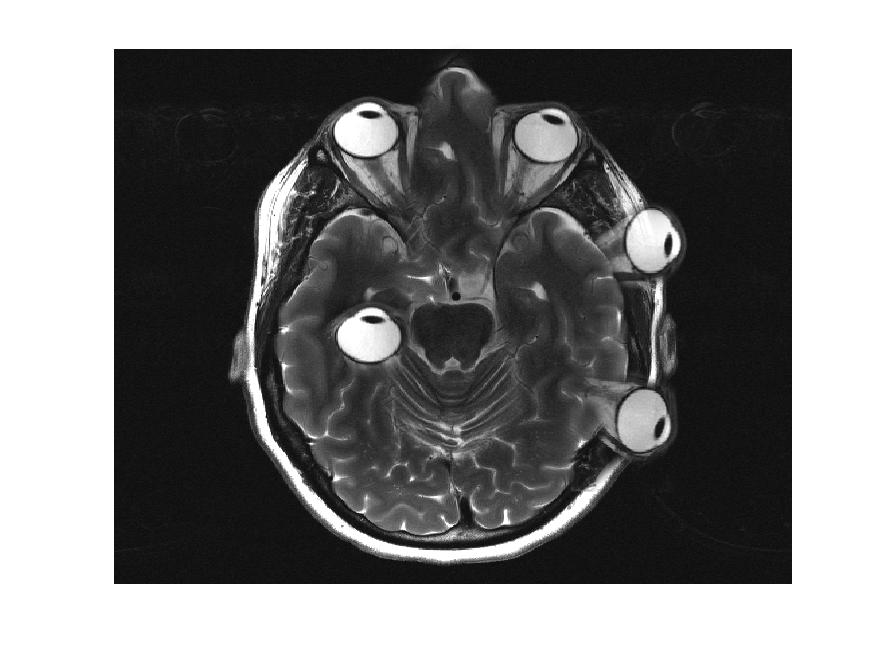

L’IRM, technique d’imagerie médicale non invasive, est très sensible aux mouvements du patient car l’acquisition spatiale se fait de manière ségmentée. L’information complète requiert une séquence longue. En effet, l’IRM ne fait pas directement une image comme en rayon-X (RX ou CT-scan). En IRM, Le signal de résonance magnétique mesuré est enregistrée dans l’espace des fréquences spatiales appelé “espace-K”. L’image finale utilisée par les radiologue est obtenue par “reconstruction” via une transformation mathématique, la transformée de Fourier.

SISMIK le modèle de correction

Nous proposons un système de correction de mouvement rétrospectif sur les données de mesure IRM (espace-K) appelé SISMIK qui reconstruit des images avec moins d’artéfacts de mouvements.

Le système est dit hybride entre l’intelligence artificielle et les méthode algorithmiques plus traditionnelles, combinant les avantages des deux approches.

1. Les mesures “brutes” sont montrées à un réseau de neurones convolutionnel (CNN) entraîné au préalable.

2. le CNN estime pour chaque ligne d’aquisition le déplacement relatif effectué par rapport au lignes adjacentes.

3. le réseau produit une trajectoire complètes (mouvement dans le temps) le long de l’acquisition

4. la trajectoire et les données brutes sont envoyées au second algorithme afin qu’il corrige et reconstruise les images correspondantes.